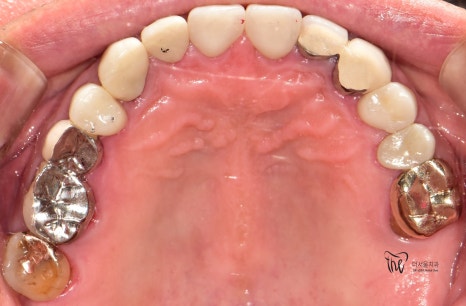

우선 교합면에서 바라보게 되면,

곳곳에 치아 결손 부위가 관찰이 되는데

이가 빠진지 시간이 꽤나 오래 되셨다는 것을

한 눈에 알아차릴 수 있습니다.

바로 결손부위를 보게 되면, 골 폭이 상당히

좁아져 있는 것을 볼 수 있는데 이는 치아 상실 후

방치 된 시간이 꽤나 오래 되었다는 것에 따른

반증이기 때문입니다.